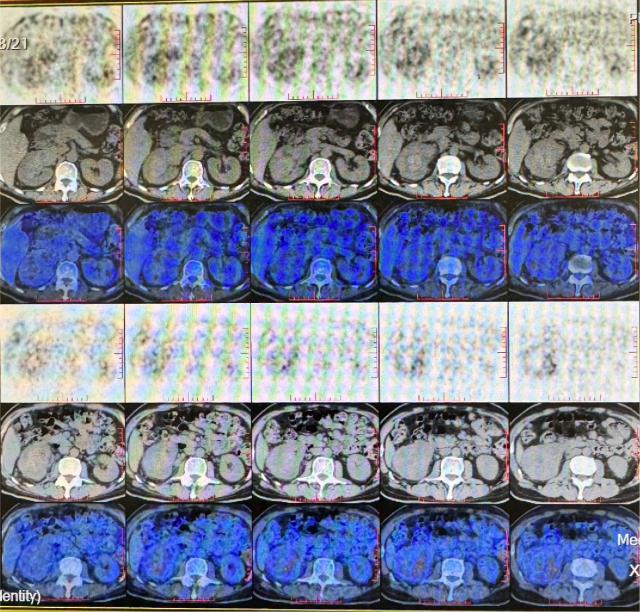

PETCT:1. 右肾中-下份混合密度软组织肿块,糖代谢轻度升高,SUVmax6.4, 右肾内糖代谢稍增高灶,SUVmax3.8,右肾癌合并肾静脉瘤栓形成;2. 右肾上腺结合部低密度灶,糖代谢轻度增高,转移瘤,SUVmax3.1。

PETCT(2022.10):1. 左侧肾上腺结节灶,糖代谢增高,转移瘤可能性大;2. 左肾多发结节状突起,糖代谢增高,考虑转移瘤,需结合增强 CT 综合判断;3. 右下肺切除术后,术区未见复发;4. 右侧胸壁局部增厚、糖代谢增高,术后改变?建议追踪。

术后病理:左肾透明细胞癌 II 级,侵及肾被膜及输尿管,肾周脂肪、左肾上腺未见癌。CT(2024.4):1. 左肾癌根治术后改变,未见术区复发;2. 左肺下叶基底段肿块、左叶间裂结节灶;3. 右肺上叶后段多发结节灶;4. 左第 3 肋、11 肋,右第 6 肋多发骨质破坏;5. 纵膈淋巴结肿大;6. 肝内多发低密度灶;7. 胰腺体尾部片状强化减低灶。

不同部位肿瘤变化情况